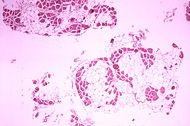

| Histopathology of gastrocnemius muscle from patient who died of pseudohypertrophic muscular dystrophy, Duchenne type. Cross section of muscle shows extensive replacement of muscle fibers by adipose cells. | |

Duchenne muscular dystrophy is caused by a mutation of the dystrophin gene at locus Xp21. Dystrophin is responsible for the connection of muscle fibers to the extracellular matrix through a protein complex containing many subunits. The absence of dystrophin permits excess calcium to penetrate the sarcolemma (cell membrane). In a complex cascading process that involves several pathways and is not clearly understood, increased oxidative stress within the cell damages the sarcolemma, eventually results in the death of the cell. Muscle fibers undergo necrosis and are ultimately replaced with adipose and connective tissue.